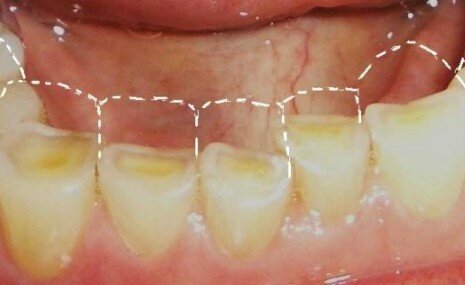

На фото пациент с патологической стираемостью зубов.